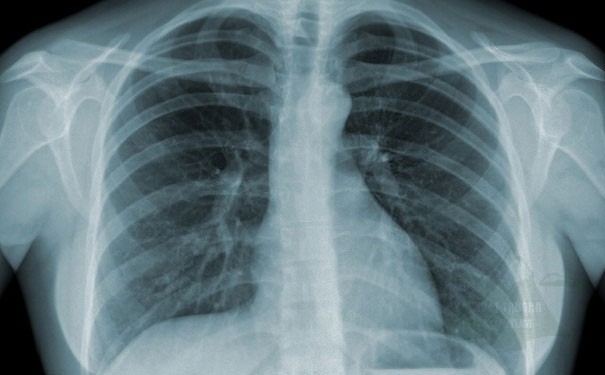

Chụp X quang là kỹ thuật chẩn đoán hình ảnh rất phổ biến để khảo sát xương và một số mô khác.

X quang là một loại bức xạ năng lượng cao. Một máy chụp X quang phát ra các chùm tia X. Các tia X xuyên qua các mô mềm và thành phần dịch (chất lỏng) trong cơ thể một cách dễ dàng . Tuy nhiên, các mô đặc như xương sẽ cản một số tia X lại. Đậm độ hay độ đậm đặc (density) có nghĩa là số vật chất có trong một khoảng không gian nhất định. Mô càng đặc (tức đậm độ cao) thì càng cho ít tia X xuyên qua. Không khí và nước ít đặc (tức đậm độ thấp) vì các phần tử cấu thành không liên kết chặt chẽ với nhau.

Phim X quang, cũng tương tự như phim chụp hình, được đặt phía sau bộ phận cơ thể cần chụp. Máy X quang sẽ chiếu tia X qua bộ phận cơ thể này. Các tia X nào gặp phim sẽ tạo hình. Càng nhiều tia X đến phim thì hình ghi được càng đen hơn. Vì vậy, các bộ phận đặc của cơ thể cản rất nhiều tia X sẽ cho hình trắng (ví dụ như xương) trong khi những bộ phận cơ thể rỗng hoặc đầy khí sẽ cho hình đen (ví dụ như phổi). Các mô mềm (ví dụ như cơ hoặc các tạng đặc trong cơ thể) sẽ cho hình ảnh có mức độ xám khác nhau tuỳ theo đậm độ của chúng.

Hình X quang thông thường sẽ cho thấy gì?

Xương, răng, gãy xương và các bất thường khác của xương.

Khe khớp và một số bất thường của ổ khớp, ví dụ như thoái hoá khớp.

Kích thước và hình dạng của tim. Vì vậy, có thể phát hiện được một số bệnh tim.

Thay đổi đậm độ mô mềm.

Ví dụ, một khối u phổi đặc hơn nhu mô phổi, sẽ cho thấy hình ảnh bóng mờ trên X quang. Một khối u vú đặc hơn mô vú bình thường sẽ cho thấy hình ảnh bóng mờ trên X quang vú (nhũ ảnh ).

Tụ dịch, trong phổi hoặc ruột chẳng hạn, có thể sẽ cho hình ảnh bóng mờ với độ xám khác với màu đen chứa đầy khí của nhu mô phổi bình thường hoặc ruột trống.